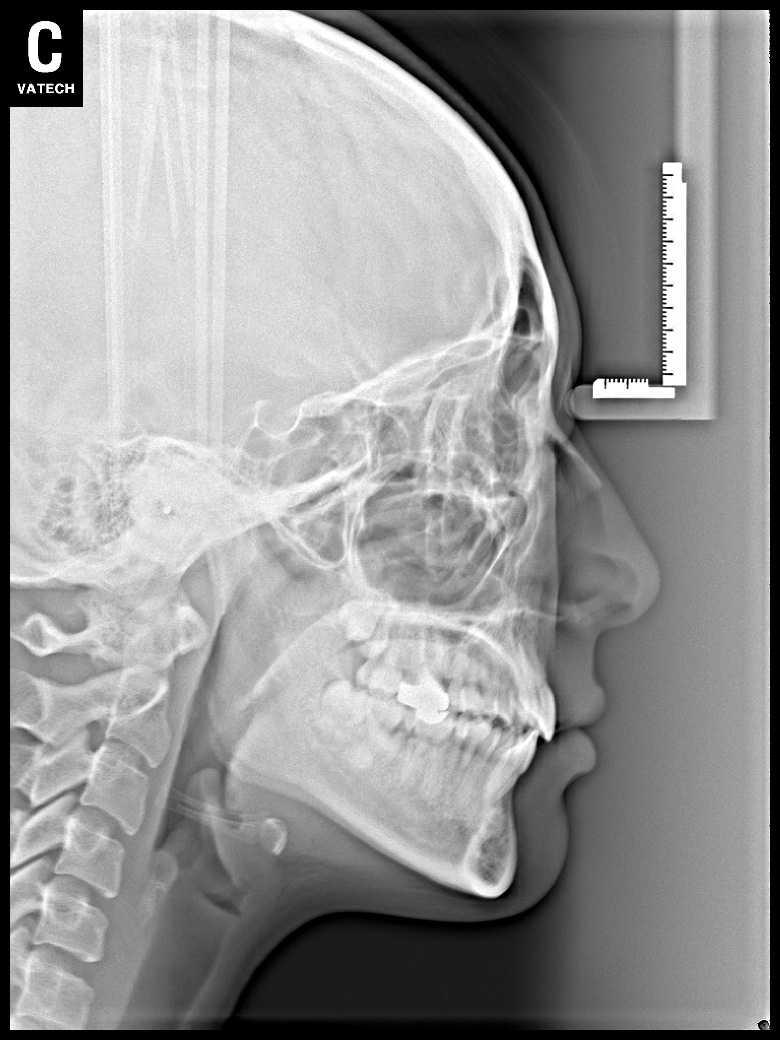

치료 전 사진입니다.